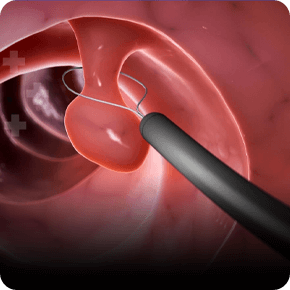

Mục tiêu tầm soát bệnh chính xác để trị hết bệnh, đem lại hạnh phúc cho người bệnh, Phòng khám đầu tư hệ thống máy móc tân tiến hiện nay, giúp bác sĩ đánh giá chính xác tổn thương và giúp sinh thiết chính xác vị trí tổn thương.

Với hệ thống máy nội soi hiện đại cùng công nghệ chẩn đoán hình ảnh tiên tiến, chúng tôi tập trung phát triển dịch vụ nội soi chuyên sâu nhằm phát hiện sớm và chính xác các bệnh lý tiêu hóa.